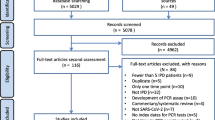

PubMed searches identified 1369 unique records for screening. The PRISMA flowchart of included studies is shown in Fig. 1. Studies that were excluded at the full-text stage are outlined (including the reason why they were excluded) in Supplementary Table 2. Data from the 16 studies that were relevant for inclusion, and their respective study characteristics, are outlined in Table 1. Study outcomes of the 16 included studies detailing correlation between SARS-CoV-2 real-time RT–PCR Ct values and epidemiological trends are summarized in Table 2, and as follows.